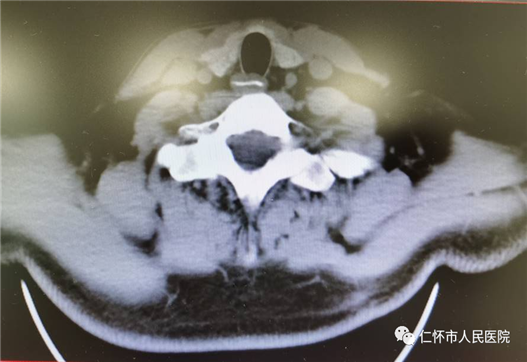

术前CT提示食管中段异物

术后CT提示未见异常